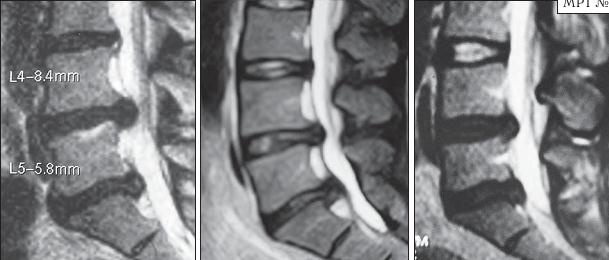

На серии снимков МРТ № 25 наблюдаются дорсальные грыжи межпозвонковых дисков в поясничном отделе позвоночника в сегментах LIV-LV Lv—SI Такие комбинации, в которых образуются по нескольку грыж, межпозвонковых дисков одновременно, случаются довольно часто на более поздних стадиях развития дегенеративно-дистрофического процесса. В общем, беда не приходит одна, «несчастье» любит, компанию МРТ № 26

На серии МРТ № 26 наблюдаются секвестрированные грыжи межпозвонковых дисков в поясничном отделе позвоночника в сегментах LIV—LV LV—SI с каудальной (каудальной — расположенной ближе к нижней части туловища, направленной вниз) миграцией секвестра (фрагментов межпозвонкового диска) МРТ № 27 ![]() На серии МРТ № 27 наблюдаются секвестрированные грыжи межпозвонковых дисков в поясничном отделе позвоночника в сегментах L]-Sl с краниальной (вверх) миграцией секвестра (фрагментов межпозвонкового диска) Должен заметить, что по моим наблюдениям, к сожалению, практически все существующие на сегодняшний день методы лечения дегенеративно-дистрофического процесса, в том числе и осложнённого грыжами межпозвонковых дисков, направлены на устранение болевого синдрома. Проще говоря, лечат следствие, а не причину! Обращаю ваше внимание на следующий факт. Бывают грыжи межпозвонковых дисков, которые не вызывают никакой симптоматики, так называемые «немые» грыжи. Как правило, они имеют срединную локализацию. Некоторые «специалисты», практикующие в области вертебрологии, ошибочно считают, что такие грыжи абсолютно безопасны и лечить их нет необходимости. При этом навязывают своё (в данном случае необоснованное, ошибочное) мнение, что межпозвонковые грыжи опасны лишь тогда, когда вызывают боли. К сожалению, это далеко не так! МРТ № 28